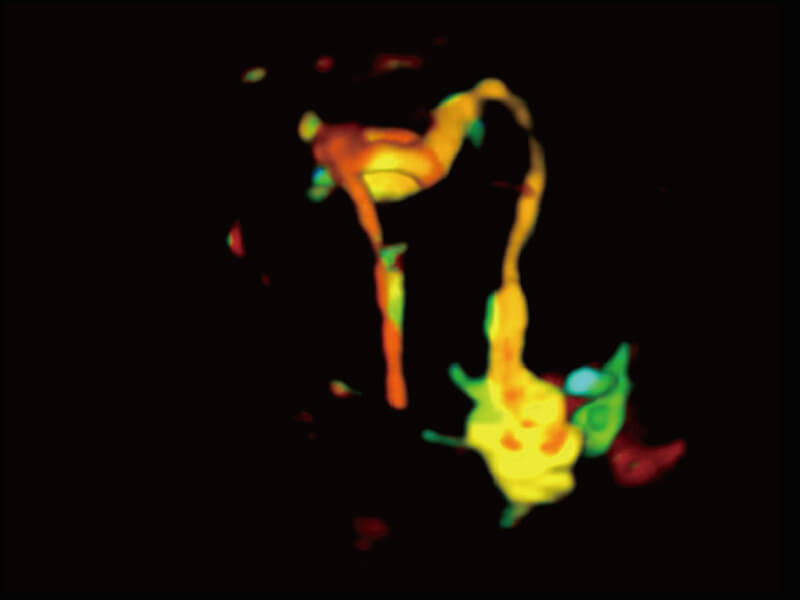

成像功能

性能优异的硬件架构,极大提升超声系统的运行效率和数据处理能力。相比以往超声成像系统,Wis+平台为您带来极快的响应速度和成像帧频,提升检查流畅度。

S60探头工艺,从前端信号处理每一个环节采集无损声学数据,真实还原组织原貌,再现解剖细节。